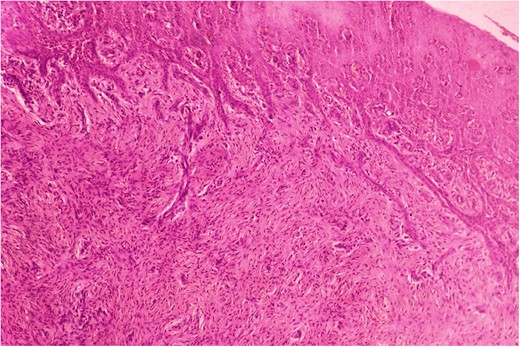

Biopsy was taken from hypertrophied and ulcerated lesion. On microscopy, tissue was lined by keratinized stratified squamous epithelium with surface ulceration. Underlying stroma showed infiltrating squamous cell carcinoma (SCC) along with extensive collagenous fibrosis (Fig. 2). Dense acute and chronic inflammations were also noted. A diagnosis of SCC with familial gingival fibromatosis was given (Fig. 3).

Histopathological picture showing infiltrating squamous cell carcinoma along with bundles of collagenous fibrous connective tissue. (H&E, ×400).